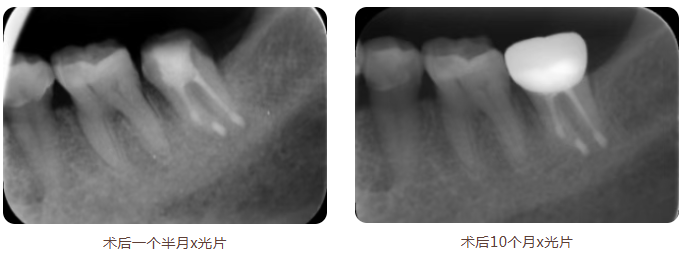

术后,郑女士恢复顺利。牙齿稳定愈合,并在约10个月后完成了牙冠修复,恢复了咀嚼功能。

经过术后近三年的定期复查,该牙齿情况稳定,治疗效果得以确认,最终保住了这颗天然牙。郑女士专程送来锦旗,表达对医疗团队的感谢。